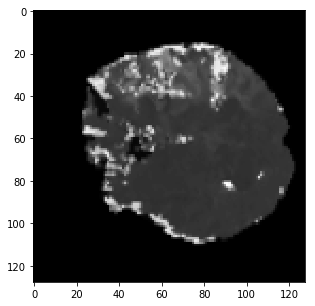

The qualitative results are shown in Fig. 2. Addition of LS and BD losses while training the network significantly improves the boundary delineation in the results. This improvement is more drastic when the network is adversarially trained as seen in the results of the proposed method as compared to BL7.

[TMax]

\subfigure[TTP]

\subfigure[DWI]

\subfigure[GT]

[BL3]

\subfigure[BL4]

\subfigure[BL7]

\subfigure[Proposed]